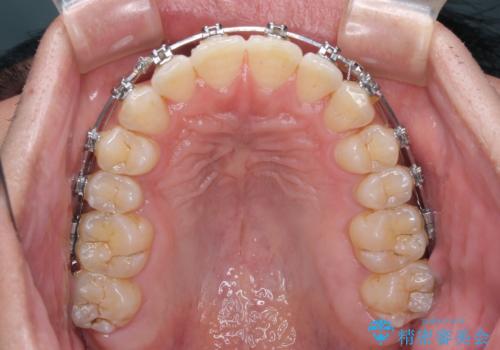

- メタルブラケット

- 1年4ヶ月

- 前歯のデコボコを気にして来院された患者様です。

インビザラインによるマウスピース矯正も適用となる歯列でしたが、できる限り自己管理の煩わしさのない状態で治したいとのことで、ワイヤー装置にて矯正治療を行うこととしました。

予定していた期間より長くかかりましたが、1年強できれいな歯列に仕上がりました。